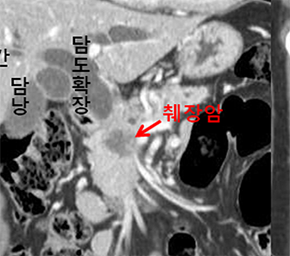

검사방법에 대하여 살펴보겠습니다. 최근에는 췌장암 검사에 내시경 초음파 검사가 많이 분비되기도 합니다 진단에 정확도가 아주 높으면서 조직검사도 또한 시행이 가능하다고 하더라고요. 췌장 종양과 만성 췌장염의 감별도 가능하고 정도가 작은 종양 진단도 내시경 초음파 검사가 가능하다고 하더라고요. 췌장암 초기증상을 보이는 경우 병원을 내방하면 CT복부 촬영을 통해 확인을 합니다. 가장 간단하고 판별이 가능한 검사방법이라고 합니다. 물론 초음파 검사를 미리감치 할 경우도 있겠으나 초음파 검사는 검사하는 분들의 재능에 따라 판단이 큽니다. CT복부 촬영으로 판단이 힘든 경우에는 MRI 검사가 시행이 되는 기질이 있어요. MRI눈 췌관, 담관도 관찰이 가능해서 간 전이도 확인이 되는 검사 합니다.